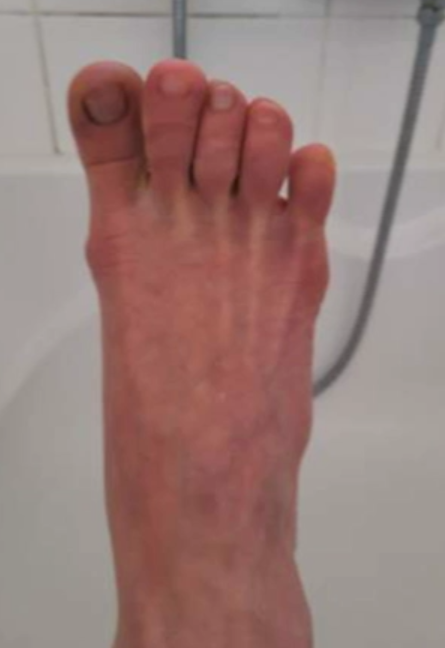

■코로나 발 - 발가락까지 얼려버린 코로나19 바이러스.

코로나19 확산 초기, 유럽국가에서 코로나19 확진자가 폭발적으로 늘어났다. 한 차례 코로나19 폭풍이 휩쓸고 간 자리에 발가락 동창 증상을 호소하는 환자들이 급증했다. 프랑스 코트다쥐르 대학병원 피부과 티에리 파세롱 교수는 일명 ‘코로나 발’로 불리는 발가락 동창 증세가 코로나19와 관련이 있다는 논문을 국제학술지 JAMA를 통해 발표했다. 티에리 파세롱 교수는 KBS1<생로병사의 비밀>팀과의 인터뷰에서 ‘코로나 발’ 증상은 코로나19 바이러스에 대한 우리 몸의 면역반응이 강하게 일어날 때 생길 수 있으며 젊은 층에서 ‘코로나 발’ 증상이 더 빈번히 발생한다고 설명했다.